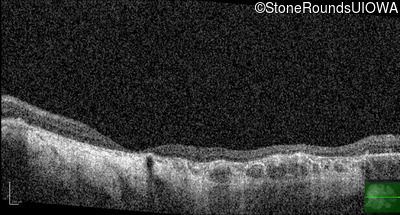

Optical Coherence Tomography - Left - 20/150

Exemplar / OCT Stack